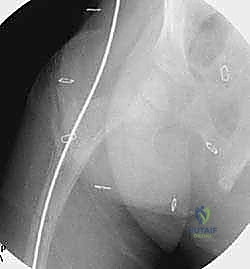

قبل العملية، يقوم الدكتور هطيف بإجراء دراسة شاملة لصور الأشعة السينية (X-rays) المأخوذة بدقة، لحساب زوايا التقوس بدقة متناهية، وتحديد نقاط بضع العظم (أماكن القص)، واختيار الحجم والطول المناسبين للمسمار التلسكوبي.

الخطوة الثالثة: بضع العظم المتعدد عبر الجلد (Multiple Percutaneous Osteotomies)

بدلاً من فتح الساق بالكامل، يقوم الدكتور هطيف بعمل ثقوب صغيرة جداً (مليمترات) في الجلد. باستخدام أدوات دقيقة جداً (مثل الإزميل الدقيق أو المثقاب المتخصص)، يتم قطع العظم في أماكن التقوس من الداخل دون إتلاف الأنسجة الرخوة أو العضلات المحيطة. هذا يحافظ على التروية الدموية للعظم (Periosteum)، مما يسرع من التئام العظم بشكل مذهل.

الخطوة الرابعة: إدخال المسمار التلسكوبي

بعد تقويم العظم وجعله مستقيماً كحبات المسبحة على خيط، يتم إدخال السلك الدليلي (Guide Wire). ثم يتم إدخال الجزء الخارجي (الأنثوي) من المسمار التلسكوبي وتثبيته في الجزء العلوي من العظم (Epiphysis).

بعد ذلك، يتم إدخال الجزء الداخلي (الذكري) من المسمار عبر الجزء السفلي من العظم وتثبيته في المشاشة السفلية. هذا التصميم العبقري يضمن حماية العظم بالكامل من الداخل.